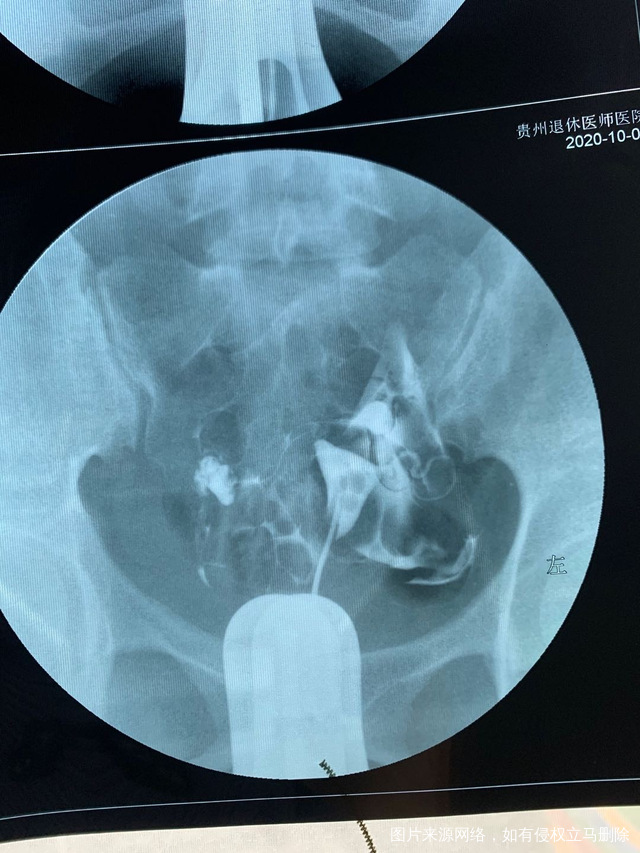

做完输卵管造影第六天了小腹还是感觉沉甸甸的如

可以热敷腹部,如果有发热,腹痛加剧,白带量多,有异味,随时就医